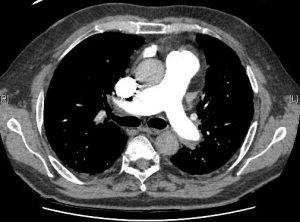

La Hipertensión Arterial Pulmonar es una enfermedad grave que afecta a la arterias pulmonares. Suele aparecer entre la 3ª y 4ª década de la vida y